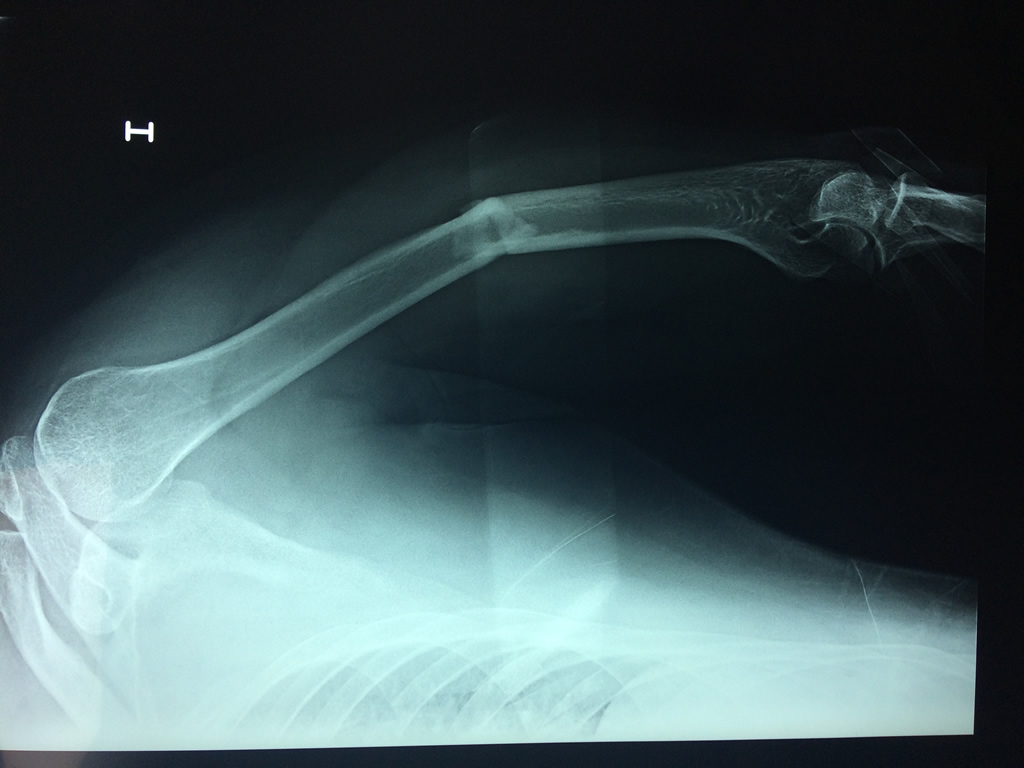

El Húmero (en latín, humerus) es el hueso más largo de las extremidades superiores en el ser humano.  Forma parte del esqueleto apendicular superior y está ubicado en la región del brazo. ... El extremo proximal del húmero tiene la cabeza, cuellos quirúrgico y anatómico y tubérculos mayor y menor.